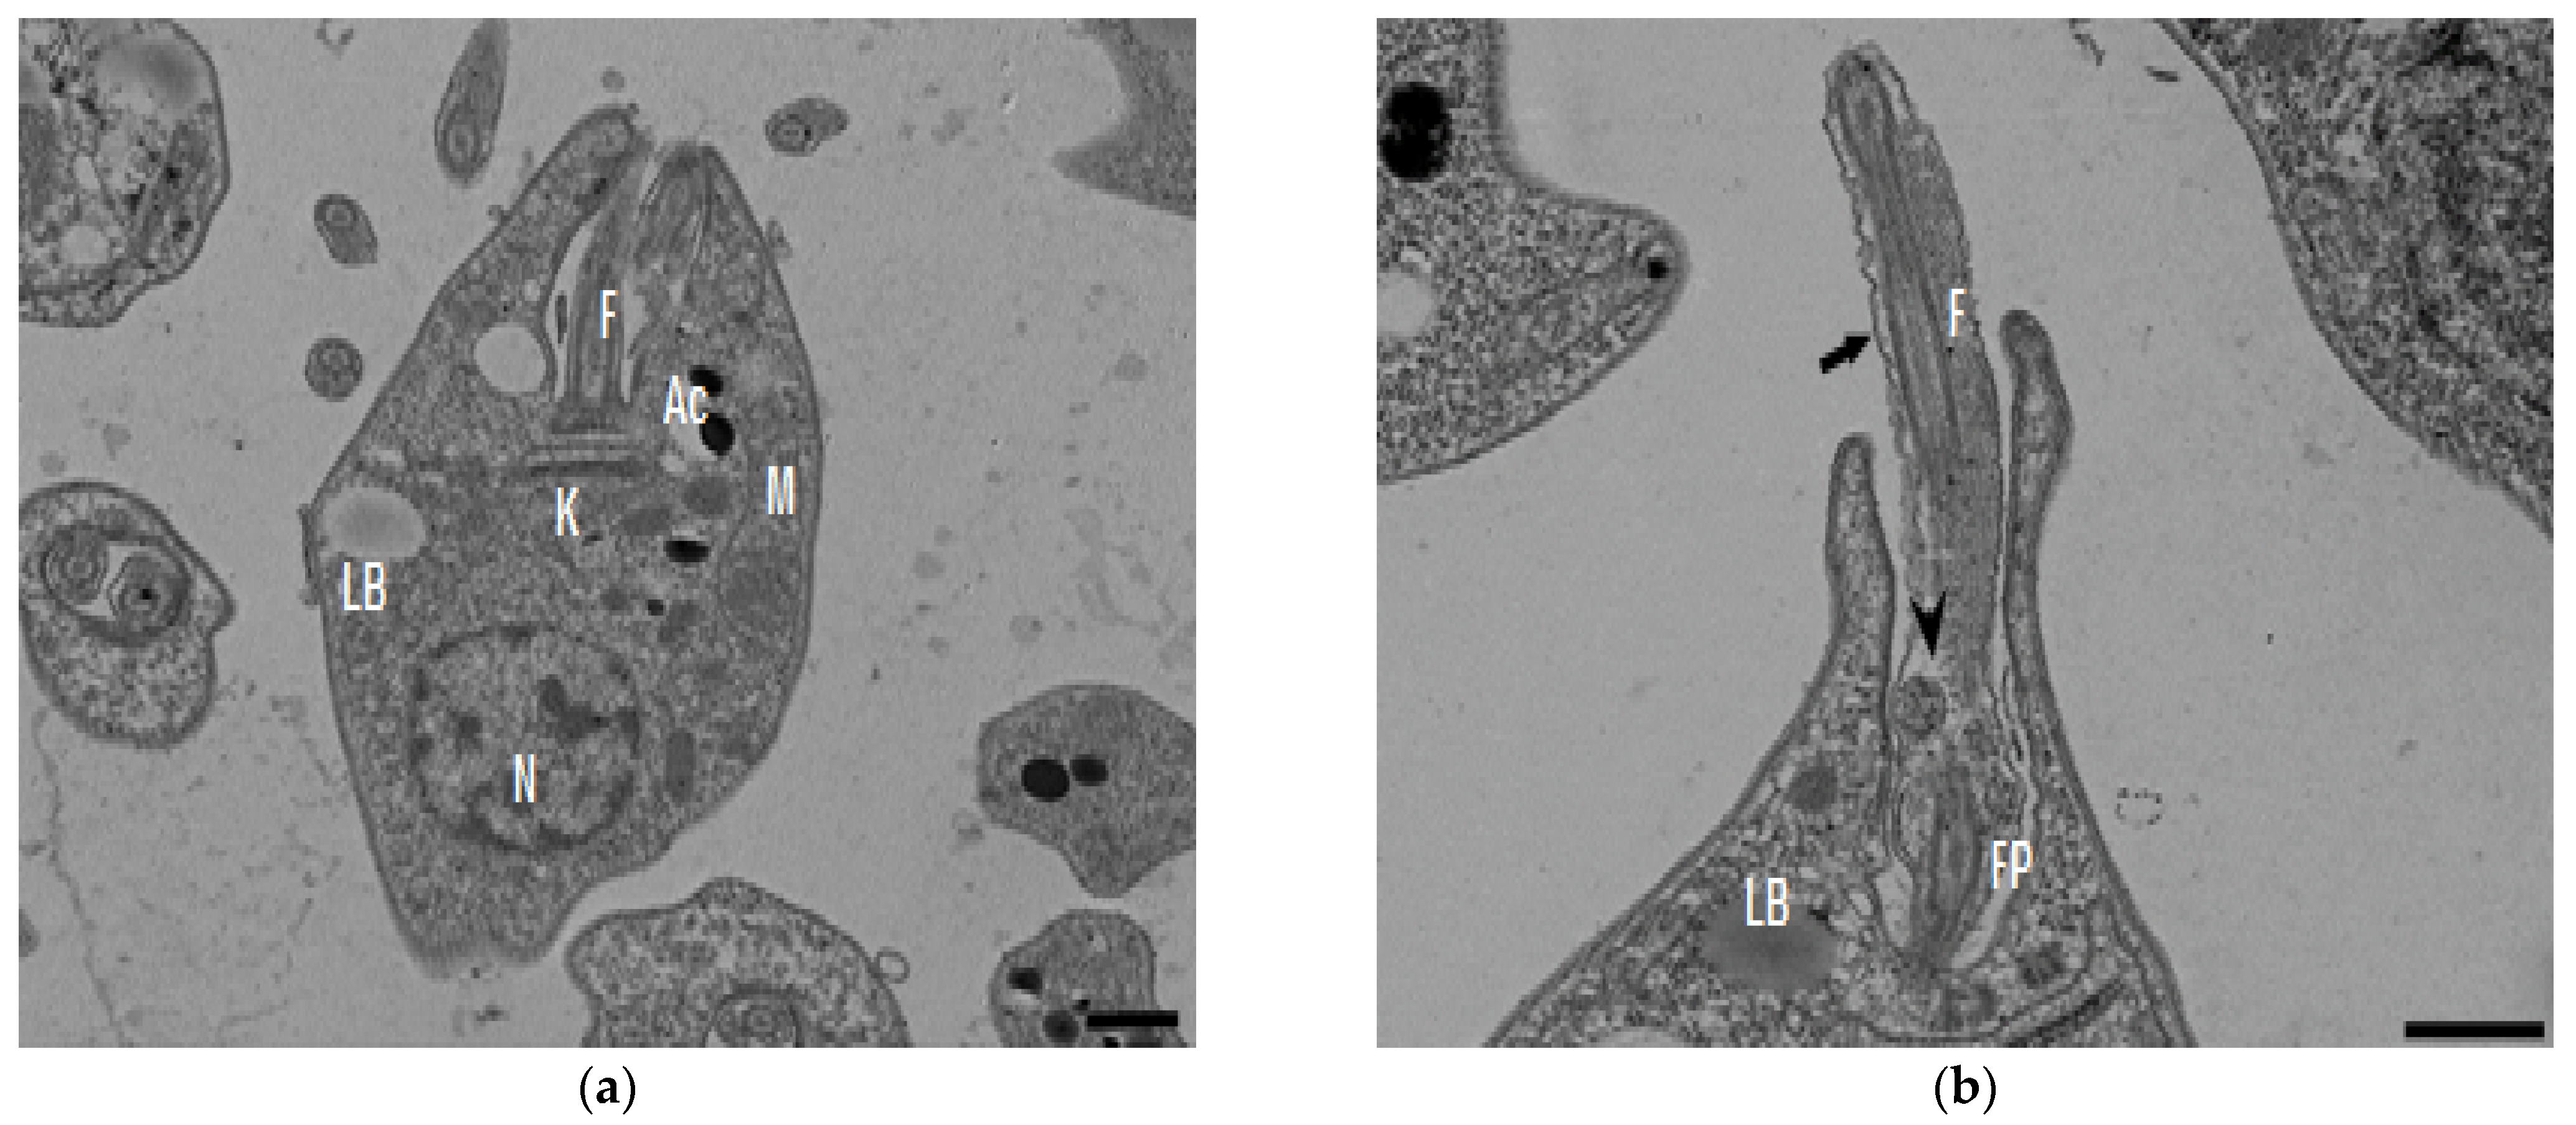

2.2. Transmission Electronic Microscopy

In the TEM studies (Figure 2), the control parasites were found to have plasma membranes and their characteristic structures without any damage (Figure 2a). However, the parasites treated for 6 h at 0.32 µM showed some early effects induced by compound 8 (Figure 2b–d). Some ultrastructural changes were evident such as the formation of autophagosomes and mitochondrion swelling with the presence of concentric membranal structures inside as well as an exocytic activity in the flagellar pocket, detachment of the flagellar membrane and alterations in the kinetoplast. Meanwhile, at 3.2 µM for 12 h (Figure 2e–h), the treated parasites showed even more profound changes such as the presence of increased vacuolization and autophagosomes, cytoplasmic myelin-like figures, plasma membrane detachment, rupture of the nuclear membrane and abnormal chromatin condensation. Total mitochondrion disorganization with swelling and concentrical membranes inside and, in some cases, the loss of cell integrity and cytosolic content were also observed.

Figure 2.

TEM analysis of L. mexicana promastigotes: non-treated (a) and treated with compound 8 at 0.32 µM 6 h (b–d) and 3.2 µM for 12 h (e–h). Control parasites show a normal morphology. Parasites treated with compound 8 show the presence of autophagosomes (APs) (d,f,h) and several alterations such as flagellar membrane detachment (black arrow) and exocytic activity in the flagellar pocket (black arrowhead) (b), kinetoplast structural alterations (c), mitochondrion swelling and concentric membranes inside (asterisks) (d,f,g), chromatin condensation (white arrowhead) (c,e,g,h), rupture of nuclear membrane (white arrow) (c,g,h), plasmatic membrane detachment (black arrow) (e) and cytoplasmic myelin figures (white stars) (e,g); loss of cell integrity and cytosolic content (white rhombus) (e,f); nucleus (N), mitochondrion (M), flagella (F), flagellar pocket (FP), kinetoplast (K), acidocalcisome (Ac), lipid body (LB), vacuole (V) (bar = 0.5 µm).

In the present study, with an interest in continuing the characterization of compound 8’s leishmanicidal activity, SEM studies were performed. It was demonstrated that compound 8 induced important ultrastructural changes in L. mexicana promastigotes such as membrane blebbing resembling an apoptotic-like process [20] and alterations in the flagella structure. In addition, TEM studies revealed alterations in the kinetoplast structure and profound mitochondrion damage including swelling and the presence of concentric membranes inside the organelle. We also observed cytoplasmic myelin-like figures indicative of an autophagy process, among other changes. Similar findings were described when L. amazonensis promastigotes were treated with Miltefosine [20], antifungal azoles [21] and calpains inhibitors [22]. In trypanosomastids, severe mitochondrion damage as well as an intense autophagy process and subsequent apoptosis cell death was related to a significant increase in reactive oxygen and nitrogen species (ROS and RNS) [23]. Parasites are exposed to extracellular ROS during their entire life cycle in the insect vector, as well as during the invasion of mammalian host cells [24], but ROS are also produced within the parasite through its electron transport chain or drug detoxification. In the present study, it was demonstrated that compound 8 triggers the production of ROS and parasite apoptosis, indicating that intracellular ROS production induced with compound 8 could be related to mitochondrial damage, as well as membrane blebbing and myelin-like figures observed in the SEM and TEM studies. Parasite apoptosis induced with compound 8 was demonstrated in the flow cytometry studies.